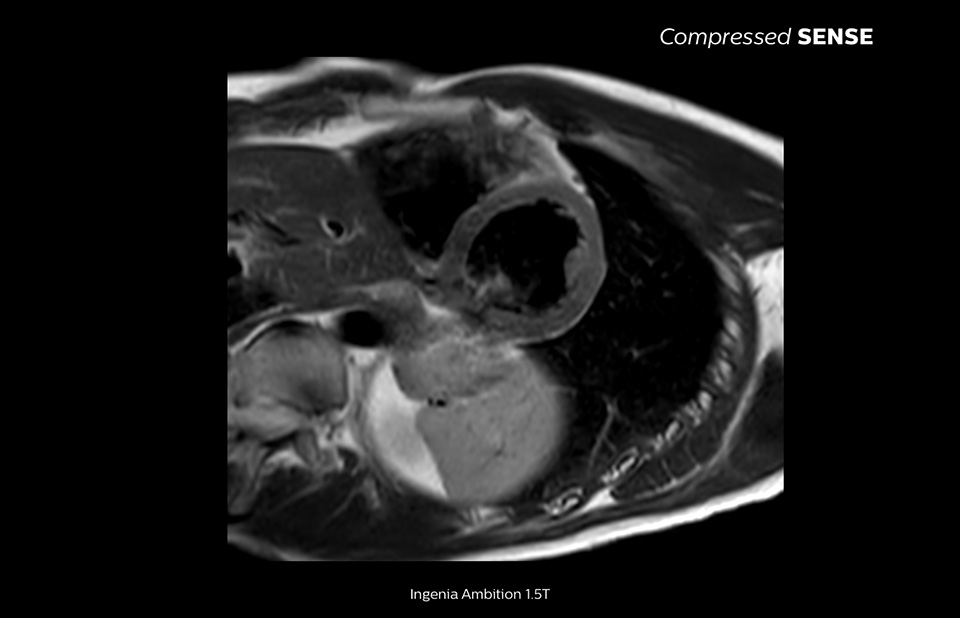

Compressed SENSE reduces SAR which is better for the patient and which gives you more confidence to accept challenging patients.

Patients with metal implants and other conditions can present challenges for MRI scanning because of the specified SAR levels required. By integrating Compressed SENSE into your ExamCard, you can reduce your total MRI exam time so that the SAR remains within the limits as specified by the MR Conditional implant manufacturer. This can allow you to scan patients who might otherwise not be accepted for an MRI scan. It also promotes greater patient comfort by shortening the scanning time.

The MRI staff at Kurashiki Central Hospital incorporated Compressed SENSE into most of the brain, spine, abdominal, and cardiac examination protocols on their Ingenia 1.5T, resulting in fast and high-quality MRI scans, which is welcomed by patients and staff.